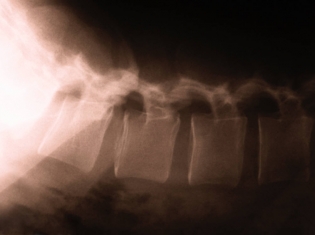

(RxWiki News) Spinal cord injuries rarely heal fully, which can lead to permanent paralysis or impairment. Lost function was believed to come from scar tissue. Research suggests there may be another explanation.

After a central nervous system injury, neurons are lost and mostly replaced by scar tissue, often referred to as the glial scar because of the abundance of glial cells. Karolinska Institutet investigators have found that most scar cells in the damaged spinal cord are actually derived from a small group of cells along blood vessels and are not glial cells as once believed.

Karolinska Institutet professor Jonas Frisé and his team of researchers demonstrated that the majority of scar cells in the damaged spinal cord are from pericytes, a small group of cells along blood vessels. There are indications that the scars stabilize the tissue and prevents regrowth of damaged nerve fibers.

Research shows that pericytes begin dividing after an injury, allowing a mass of connective tissue cells to form a large portion of scar tissue. These cells are necessary to regain tissue integrity. When this reaction doesn't occur, holes appear in the tissue instead of scarring.